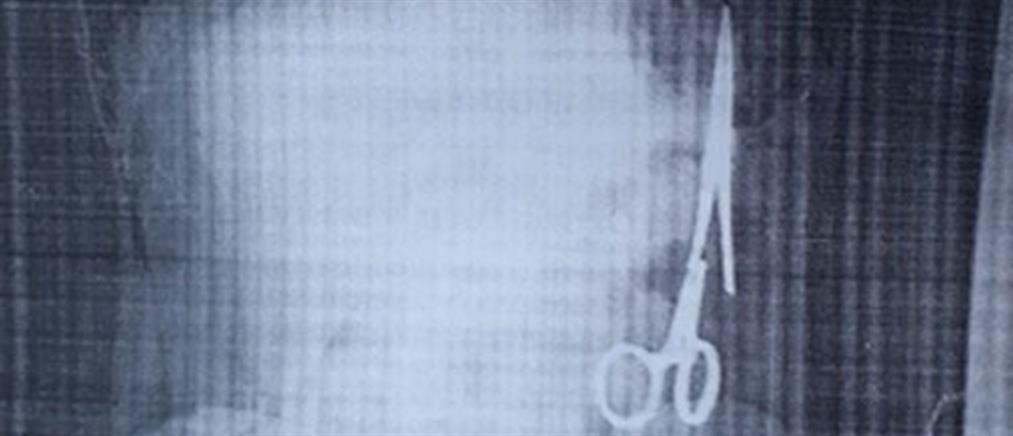

Ειδήσεις21-08-2020 22:27Λαπαροσκοπικό Γαστρικό Μανίκι (Sleeve): μόνιμη απώλεια βάρους, φυσιολογική λειτουργικότητα στομάχου